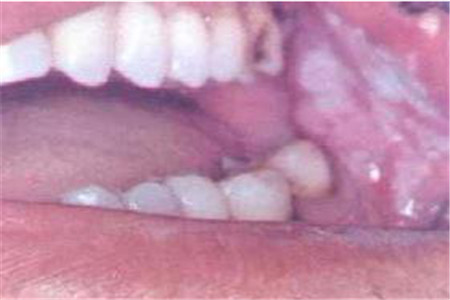

第四:口腔粘膜

其实口腔癌有一个可以葱肉眼中看出的症状哦。一般来说口腔粘膜有出现白斑或者是粘膜下有红斑,水肿等等,那这可能就是口腔癌,因此要警惕哦。